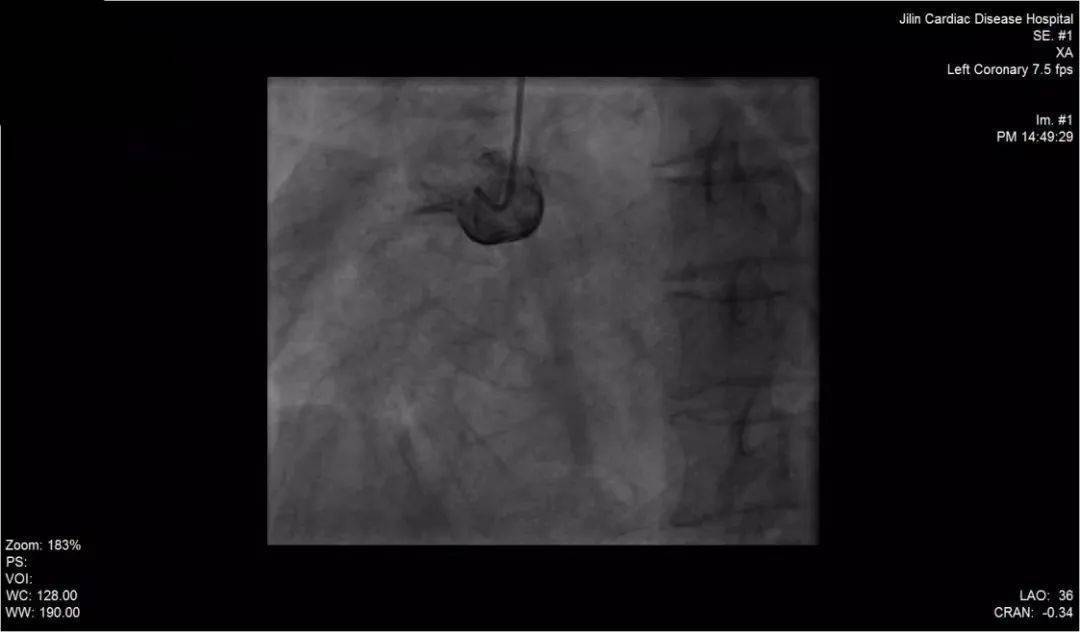

术前造影图像

急性下壁心肌梗死就是发生在心脏下壁的心肌梗死。 急性心肌梗死主要是由于冠状动脉严重狭窄或者冠状动脉紧急闭塞,导致心肌缺血缺氧坏死。